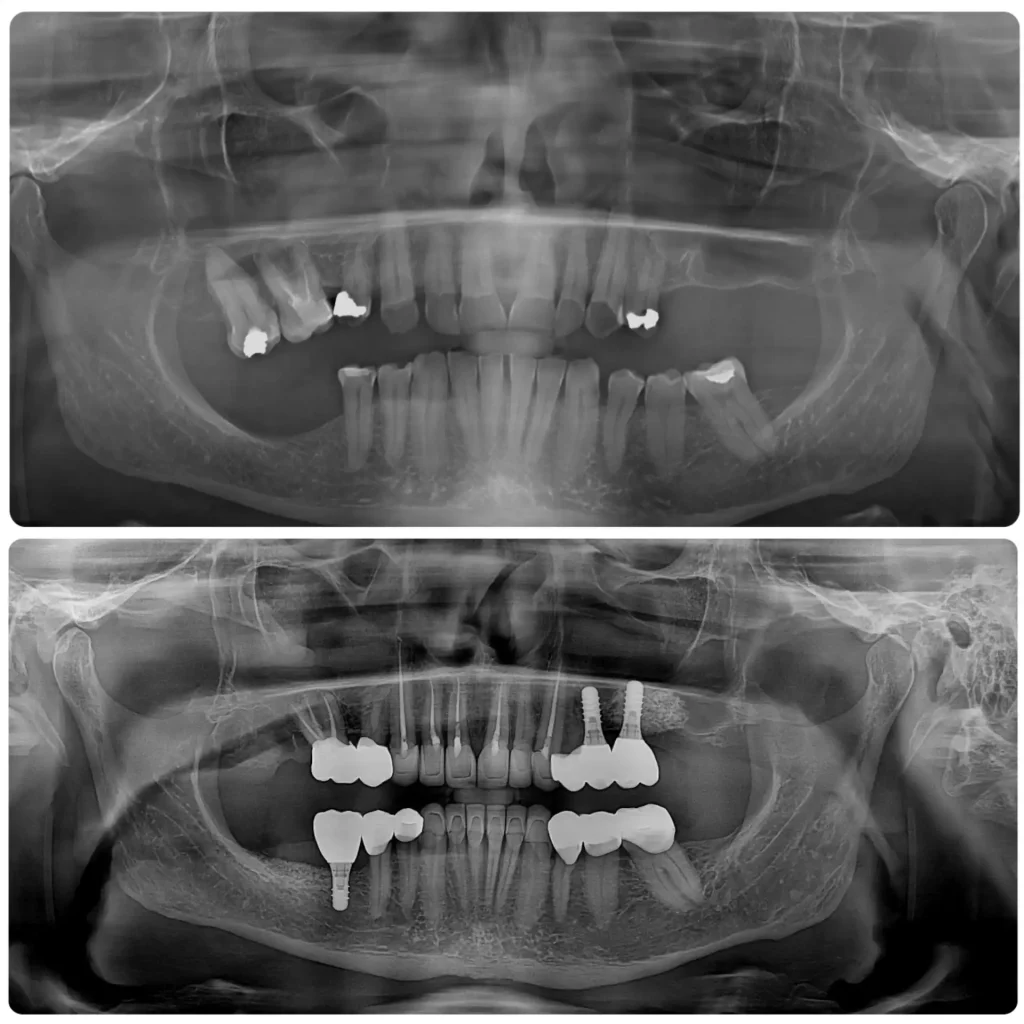

Case studies